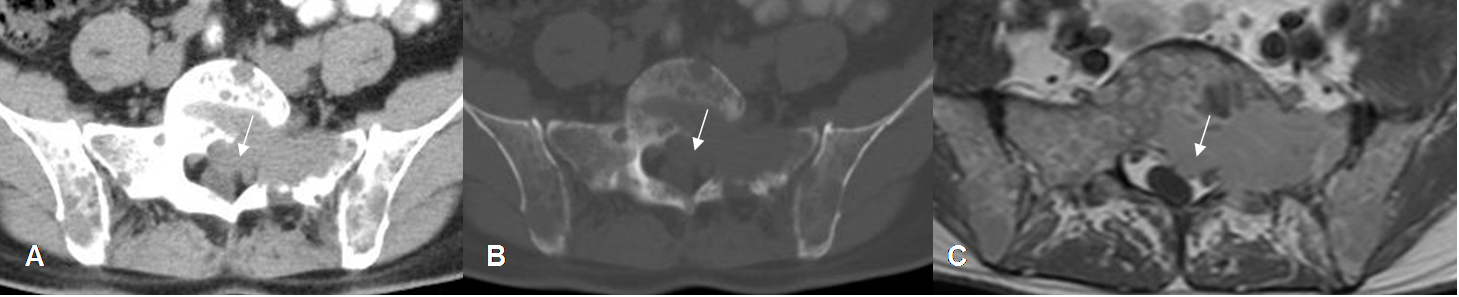

Fig 197. Mieloma.

A: TAC axial en ventana de tejido, B: TAC axial en ventana osea y C: RM axial con contraste. Múltiples lesiones líticas en el sacro y los iliacos. Se encuentra masa de tejidos blandos que realza con el contraste y comprime el saco dural en el lado izquierdo.